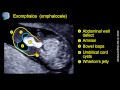

This video clip describes the ultrasound features of exomphalos (omphalocele) containing small loop of bowel at 12 weeks' gestation.

At 8--10 weeks all fetuses demonstrate herniation of the midgut that is visualized as a hyperechogenic mass in the base of the umbilical cord. Retraction into the abdomen occurs at 10--12 weeks.

For an exomphalos containing bowel only, the prevalence is about 1:100 for crown-rump length (CRL) of 45.0-54.9 mm, 1:800 for a CRL of 55-64.9 mm andand 1:2,000 for CRL of 65.0-84.0 mm. The prevalence for an exomphalos containing liver is about 1:3,500. Exomphalos containing liver persists throughout pregnancy, whereas exomphalos containing bowel only resolves by 20 weeks' gestation in about 90% of cases. Associated chromosomal abnormalities, mainly trisomy 18, are observed in 50% of cases at 11-13 weeks, compared to about 30% at mid-gestation and 15% in neonates, because trisomy 18 is associated with a high rate of intrauterine death.